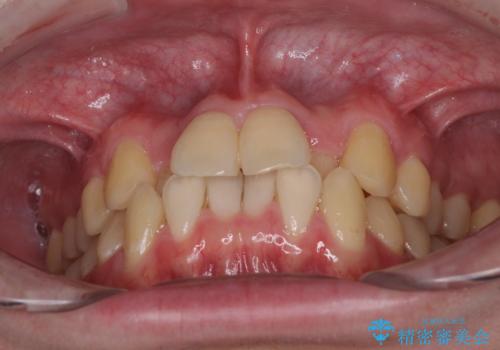

前歯のクロスバイト インビザラインによる矯正治療

- 上下のクロスバイトと前歯のデコボコを気にして来院された患者様です。

インビザラインを用い、IPR(歯と歯の間を削る)と歯列全体を拡大させることで、歯並びを整えていくこととしました。

上下ともに歯列全体を後方に移動させるため、上下の親知らずを抜歯することとしました。

奥に位置していた上の前歯が下の前歯を乗り越える際、奥歯でものを咬むことができず、辛い時期が続きました。